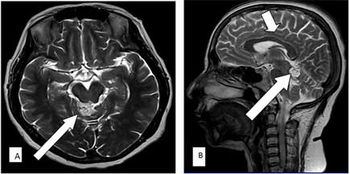

Case History: 15-month-old with focal seizure, developmental delay, disproportionate increase in size of head.